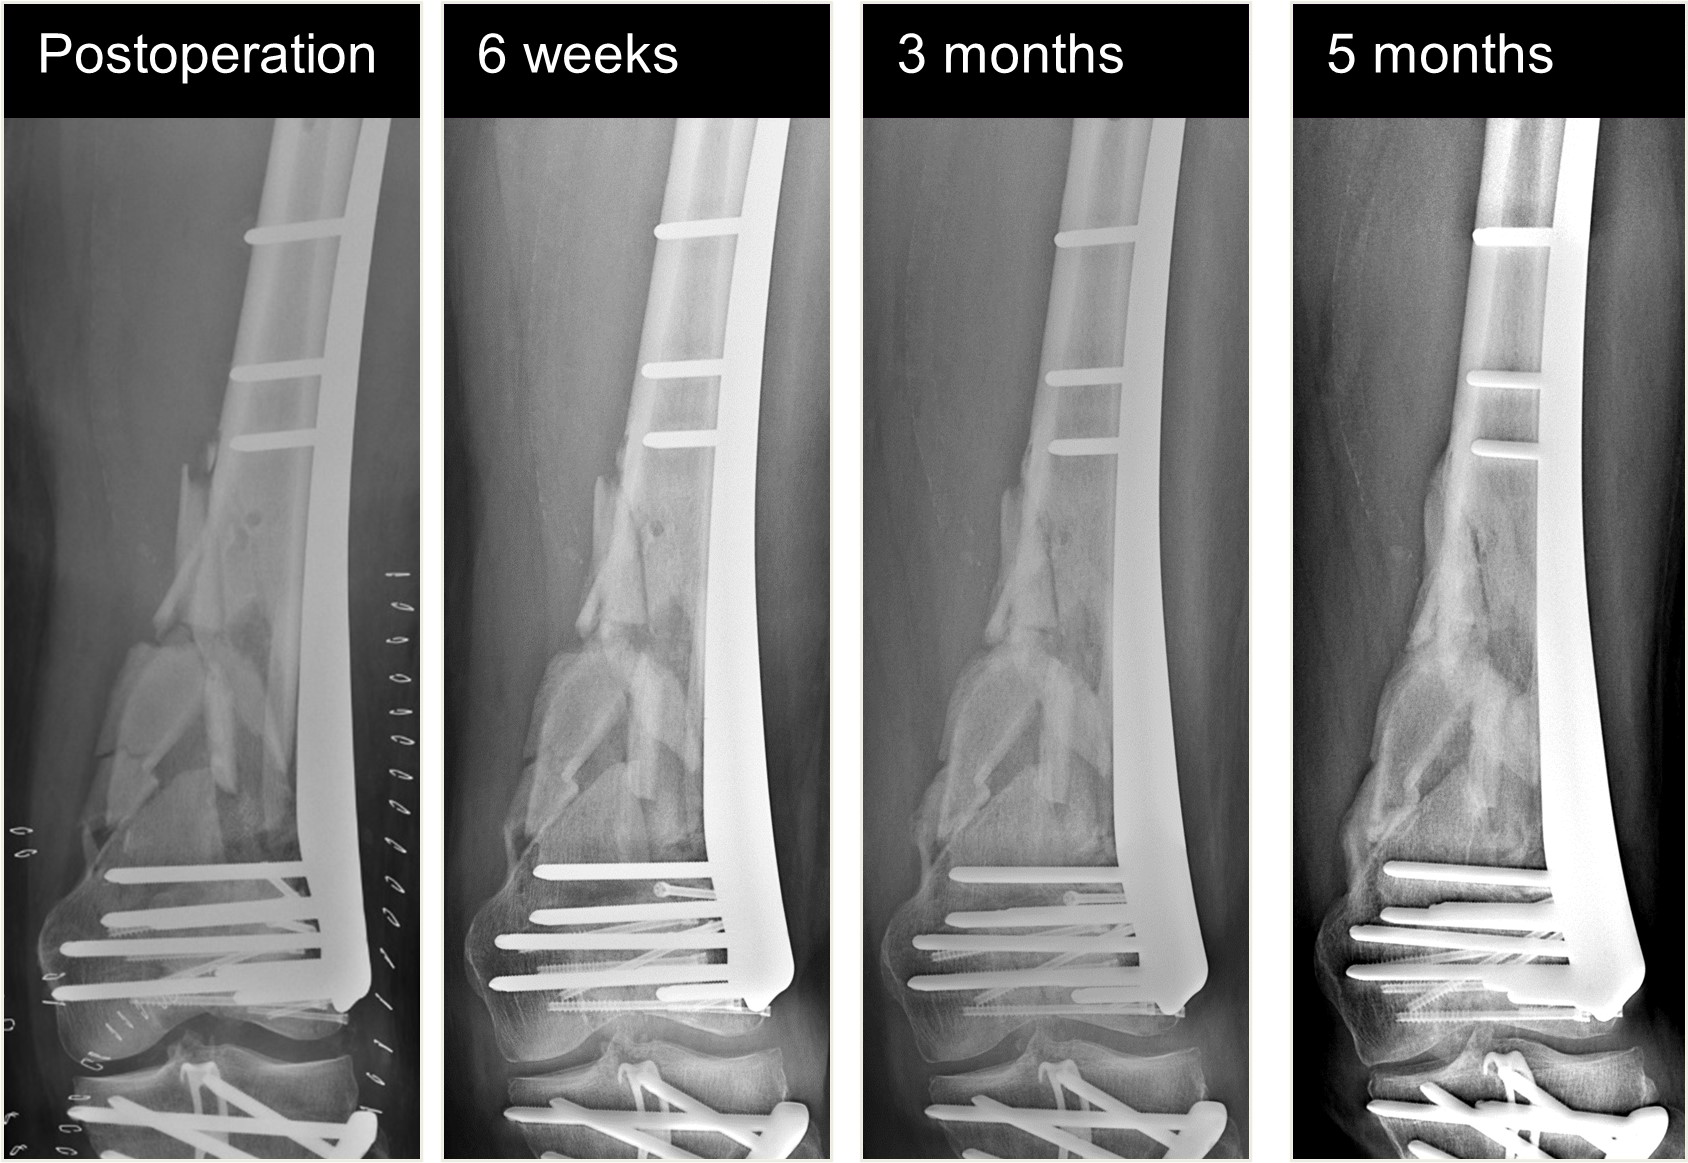

The patient healed and returned to preoperative function (Fig 7).